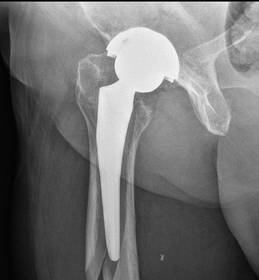

Hip replacement surgery is a medical procedure in which a surgeon removes damaged parts of a hip joint and replaces…